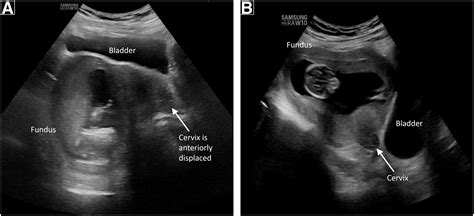

Ultrasound Imaging

Ultrasound imaging is a non-invasive technique that uses high-frequency sound waves to create images of the uterus and fetus. It is commonly used to:

• Confirm the presence of a gravid uterus

• Determine the gestational age of the fetus

• Assess fetal development and growth

• Identify any potential abnormalities or complications

Ultrasound examinations are typically performed at various stages of pregnancy to monitor the fetus's progress and detect any issues early.